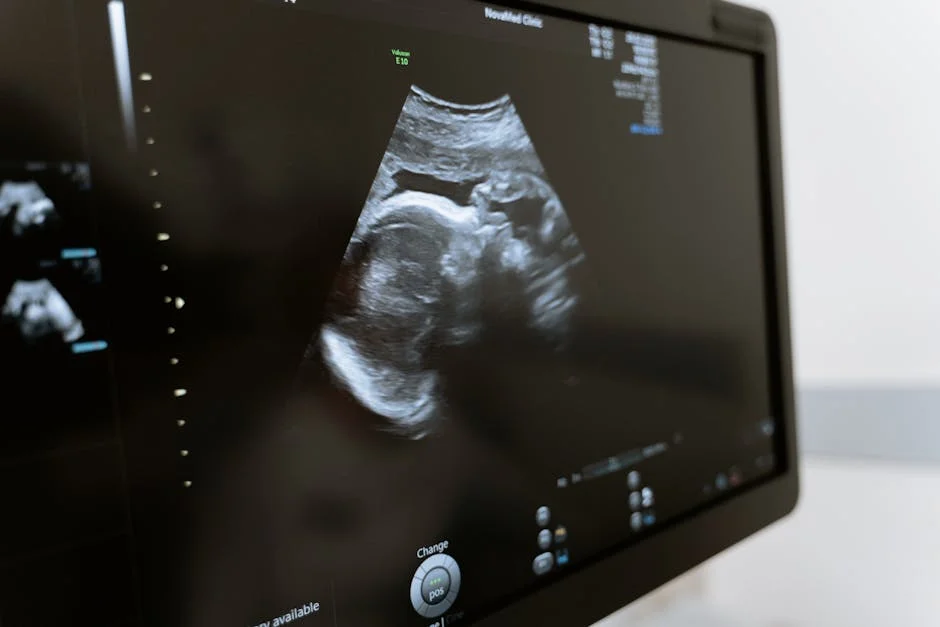

Khám lâm sàng và siêu âm đánh giá

- Siêu âm màu Doppler: Đây là xét nghiệm quan trọng. Bác sĩ sẽ kiểm tra lưu lượng máu trong dây rốn, động mạch tử cung và động mạch não của bé để đảm bảo bé vẫn nhận đủ oxy và dinh dưỡng từ nhau thai.

- Đo tim thai và theo dõi cử động thai (Monitoring): Mẹ sẽ nằm và được gắn một máy theo dõi để ghi nhận nhịp tim của bé và các cơn gò tử cung trong khoảng 20-30 phút. Điều này giúp đánh giá sức khỏe của bé và phân biệt cơn gò sinh lý với chuyển dạ thật.